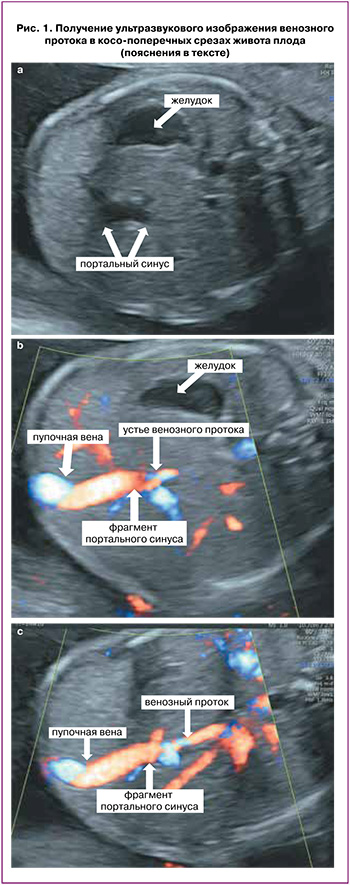

При ультразвуковом исследовании для оценки венозного протока используют средне-сагиттальный либо косопоперечный срез живота плода с использованием различных цветовых допплеровских модальностей, а также объемных режимов их реконструкции. Нормальное развитие венозного протока может быть констатировано при визуализации всех компонентов так называемого афферентно-венозного комплекса плаценты – последовательно соединяющихся пупочной и левой воротной вены, портального синуса и венозного протока.

Для осмотра данного комплекса в косопоперечном срезе после выведения стандартного поперечного среза, используемого для измерения окружности живота плода, в котором в обязательном порядке должен определяться желудок и портальный синус в виде L-образного изгиба (рис. 1а), сохраняя изображение последнего на мониторе, необходимо наклонять датчик до визуализации пупочного кольца, интраабдоминального отдела пупочной вены, портального синуса (рис. 1б), и затем отходящего от него в сторону сердца венозного протока (рис. 1с). В средне-сагиттальном сечении туловища плода также необходимо проследить непрерывную связь пупочной вены, портального синуса и венозного протока, определить место его дренирования в нижнюю полую вену под диафрагмой (рис. 2) [27, 28].